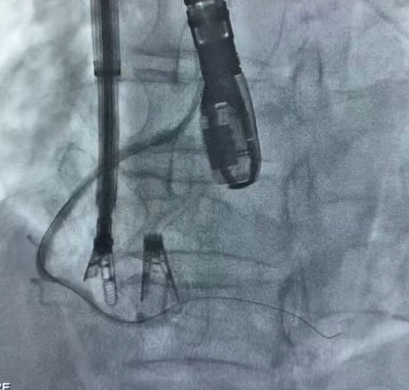

9. Postoperatively, evaluate the overall morphology and position of the clipped components using DSA.

Postoperative effect

Immediate Postoperative Echocardiographic Assessment: Tricuspid regurgitation was reduced from preoperative grade 4+ to grade 1+, the annulus diameter was reduced to 6.15 cm², and the leaflet coaptation was satisfactory.